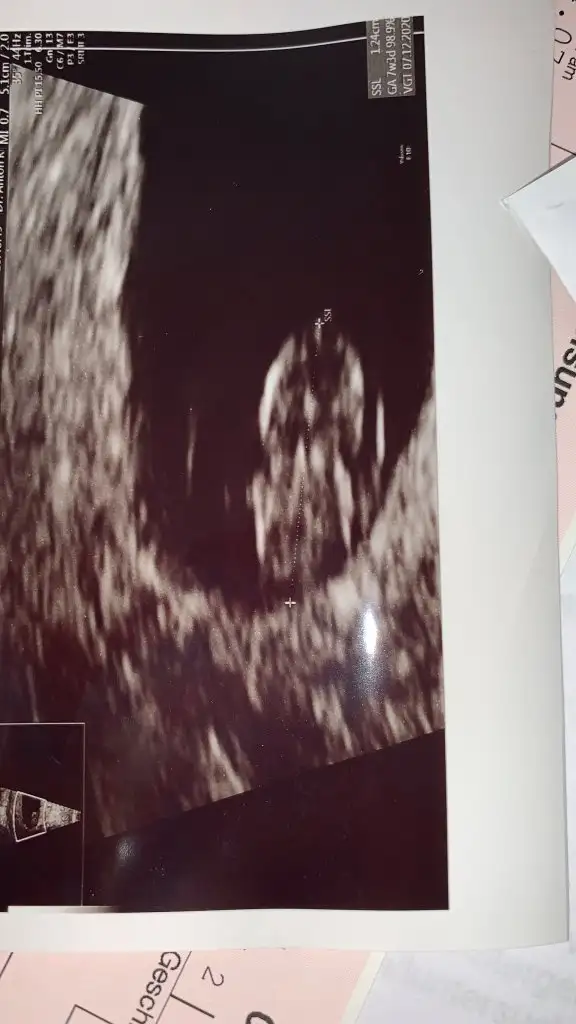

Maşallah canım mucizen çok güzel görünüyorBenim uzaylının resmini atıyım. Teyzelerimiz bugün 7+2 deyiz. Boyumuz 1,24cm. Sizlerinde yakışıklı fotolarını beklerizEki Görüntüle 2624310